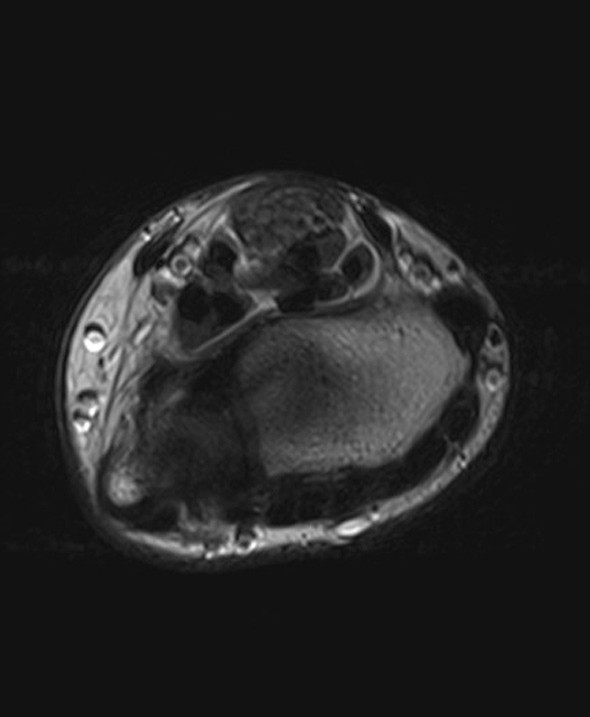

En tidligere frisk jente i tenårene ble henvist til håndkirurgisk avdeling med en kul på bøyesiden ved venstre håndledd. Denne var blitt oppdaget av mor rundt syv år tidligere og var etter hvert blitt økende smertefull. Pasienten beskrev overfølsomhet for berøring og nummenhet i tommel, peke-, lang- og ringfinger. Perkusjon over tumor ga utstrålende smerter og økt nummenhet i de samme fingrene. MR-undersøkelse viste en fortykket medianusnerve med utseende som en kabel på grunn av fibrøs fortykkelse av peri- og endonevrium og økt mengde fett som separerer de ca. 15 nerveaksonene (bilder på nett). Tumorens utbredelse var ca. 10 cm. Tilstanden ble diagnostisert som et lipofibromatøst hamartom på grunn av MR-funnene, som angis som patognomoniske for tilstanden (1).

Det ble gjort eksplorasjon av tumor og dekompresjon av nerven i karpaltunnelen. Bildet viser tumoren, som på det tykkeste hadde 3 × større diameter enn en normal nerve. Ved kontroll to og seks måneder senere hadde pasienten de samme smerteplagene som før operasjonen, men følesansen i fingrene var forbedret. Nevrografi etter to måneder viste moderat aksonal og demyeliniserende sensorimotorisk affeksjon av medianusnerven i håndledds- og håndrotsnivå, tydende på kompresjonsnevropati. EMG-undersøkelse viste sparsom denervasjonsaktivitet og funn som ved gjennomgått reinnervasjon. Det var ingen tidligere undersøkelser som man kunne sammenligne med.